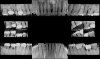

Fig 7. Pretreatment periapical radiographs.

Figure 7

Fig 8. Periapical radiograph of the maxillary right first molar (identified as the most periodontally involved molar that was planned to be maintained).

Figure 8

Periodontal examination revealed generalized BOP and PDs up to 9 mm in the maxillary and mandibular molars with multiple furcations in each molar (Figure 2 through Figure 7). He presented with class I mobility in many posterior teeth and class II mobility in teeth Nos. 3 and 9 (maxillary right first molar and maxillary left central incisor, respectively). The periodontist decided to score tooth No. 3 for the PRS, as this was the most periodontally involved molar that was planned to be treated and maintained (Figure 2 and Figure 8). This tooth (maxillary right first molar = score 1) presented with probing depths of 7 mm (score 1); three total furcation invasions (score 3) (mesial [degree II furcation], buccal [degree I furcation], and distal [degree II furcation]); and a class II mobility (score 2). The total PRS for tooth No. 3 was 8, representing a "guarded" prognosis. Based on this score, the likelihood of not losing any teeth to periodontal disease for 15 years was 81%, and for 30 years the likelihood was just 56% (Figure 9).7